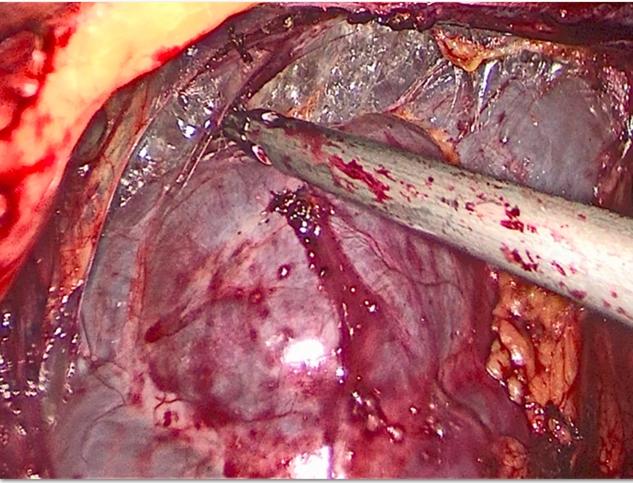

术中见左肾如皮囊样,已无正常的肾实质

皮囊肾体积过大,切开清理积水,增加腹腔镜下操作空间